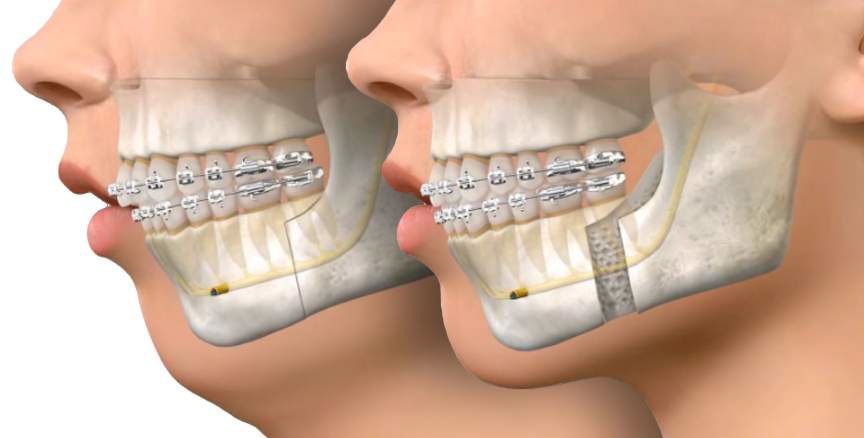

جراحی ارتوسرجری شامل تغییر درموضع فکها و ساختارهای استخوانی صورت است. هدف اصلی این جراحی، تصحیح اختلالات ساختاری فک و صورت است که باعث ناهنجاریهای دندانی و فکی شدهاند. به طور کلی، در این روش، یک متخصص ارتودنسی و یک جراح فک و صورت با همکاری همزمان و هماهنگ، برای برنامهریزی و اجرای درمان ترکیبی همکاری میکنند.

قبل از جراحی، برنامهریزی دقیقی صورت میگیرد. این شامل ارزیابی دقیق ساختارهای دندانی، فکی و صورتی، بررسی تصاویر شعاعی و مدلسازی سهبعدی است. سپس، در فرآیند جراحی، اقدام به تغییر موضع فکها، بازسازی استخوانها، بهبود تراز بیت (تماس دندانها) و اصلاح برخی اختلالات صورتی میشود. این جراحی معمولاً تحت بیهوشی کامل انجام میشود و نیازمند زمان و بازیابی دقیق پس از عمل است.

- جراحی ارتوسرجری: در این مرحله، جراح ارتوگناتیک با بیماری که تحت بیهوشی کامل قرار میگیرد، عمل جراحی را انجام میدهد. این شامل تغییر موضع فکها، بازسازی استخوانها، تصحیح تراز بیت و اصلاح برخی اختلالات صورتی میشود.

- بازیابی پس از جراحی: پس از جراحی، بیمار به مرحله بازیابی و درمان ارتودنتیکس ادامه میدهد. این شامل استفاده از اپاراتوسهای ارتودنتیکس (مانند براکتها و سیمهای ارتودنسی) جهت تراز و تعادل نهایی دندانها و ساختارهای فک و صورت است.